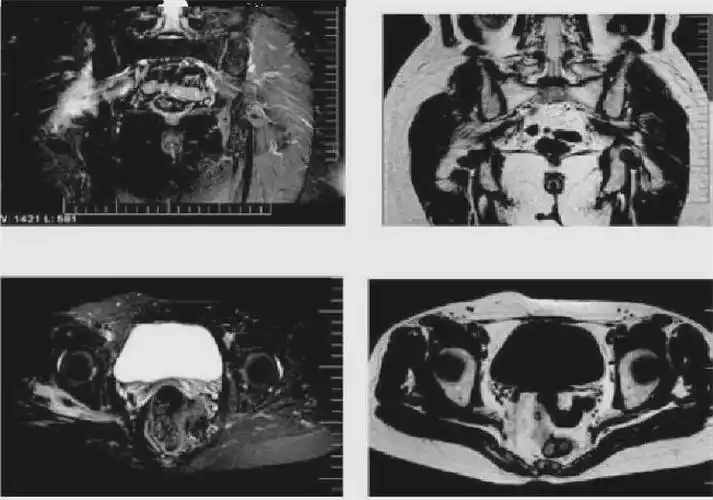

骨盆,臀部肌肉囊肿,一个盆腔,髋关节不适,疼痛的少见原因 [精华]

男性,左臀部疼痛2-3年,请诊断!